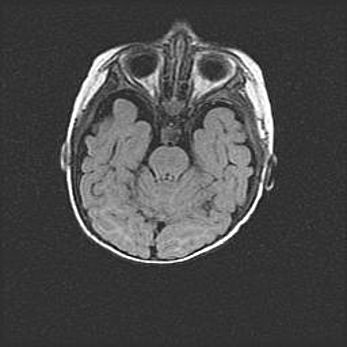

Церебральная ишемия II.

Возраст: 5 дней

Вес: 3400 г

Пол: женский

Окружность головы: 35 см

Срок гестации: 39 недель

Церебральная ишемия – это заболевание, характеризующееся недостаточностью (гипоксией) либо полным прекращением (аноксией) снабжения мозга кислородом по причине закупорки одного или нескольких сосудов. Это приводит к  что метаболическим расстройствам различной степени тяжести в тканях головного мозга, развитию коагуляционных некрозов и гибели нейронов.